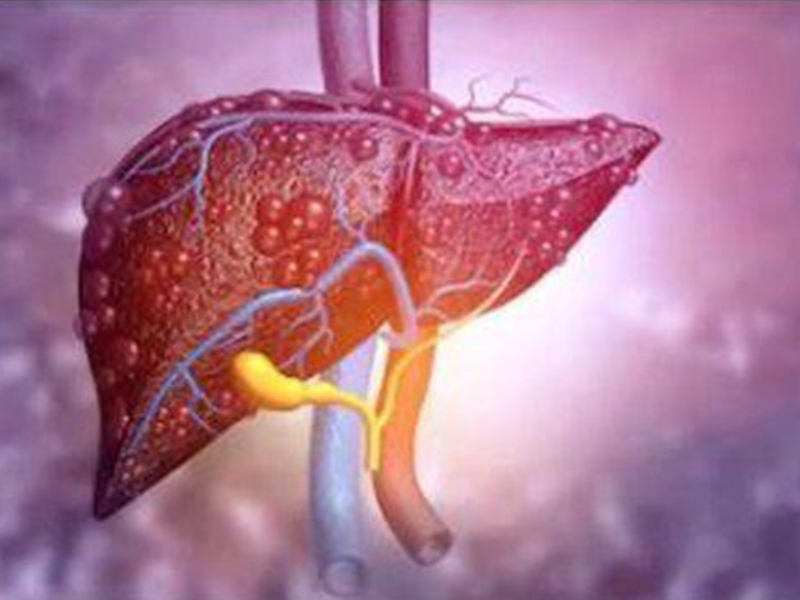

Tumors & Cancers

Discover symptoms & explore medicines and treatment options. Also read expert health articles about symptoms, the latest research, medicines and alternative treatments for every disease and medical condition.